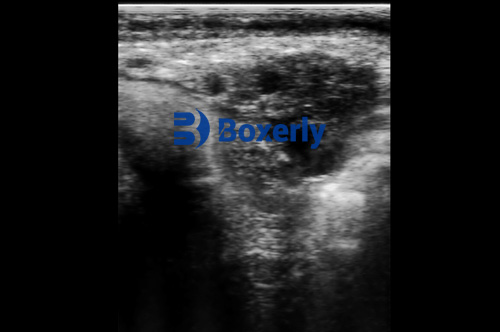

Although ultrasonography can vividly display internal anatomical structures such as the ovaries, uterus, liver, kidneys, and even fetal organs, its diagnostic accuracy is highly dependent on the operator’s skill. Unlike laboratory tests that yield numerical results, ultrasound images are real-time, greyscale visuals that must be interpreted by the veterinarian. This means extensive training is necessary to differentiate between normal and pathological findings.

The most common ultrasound mode used in animals is B-mode (brightness mode) imaging. While excellent for detecting structural changes and general shapes, it cannot provide detailed information about blood flow, tissue elasticity, or metabolic activity. In complex cases—such as differentiating between a malignant and benign uterine mass—additional tools such as Doppler ultrasonography, elastography, or CT/MRI may be required.